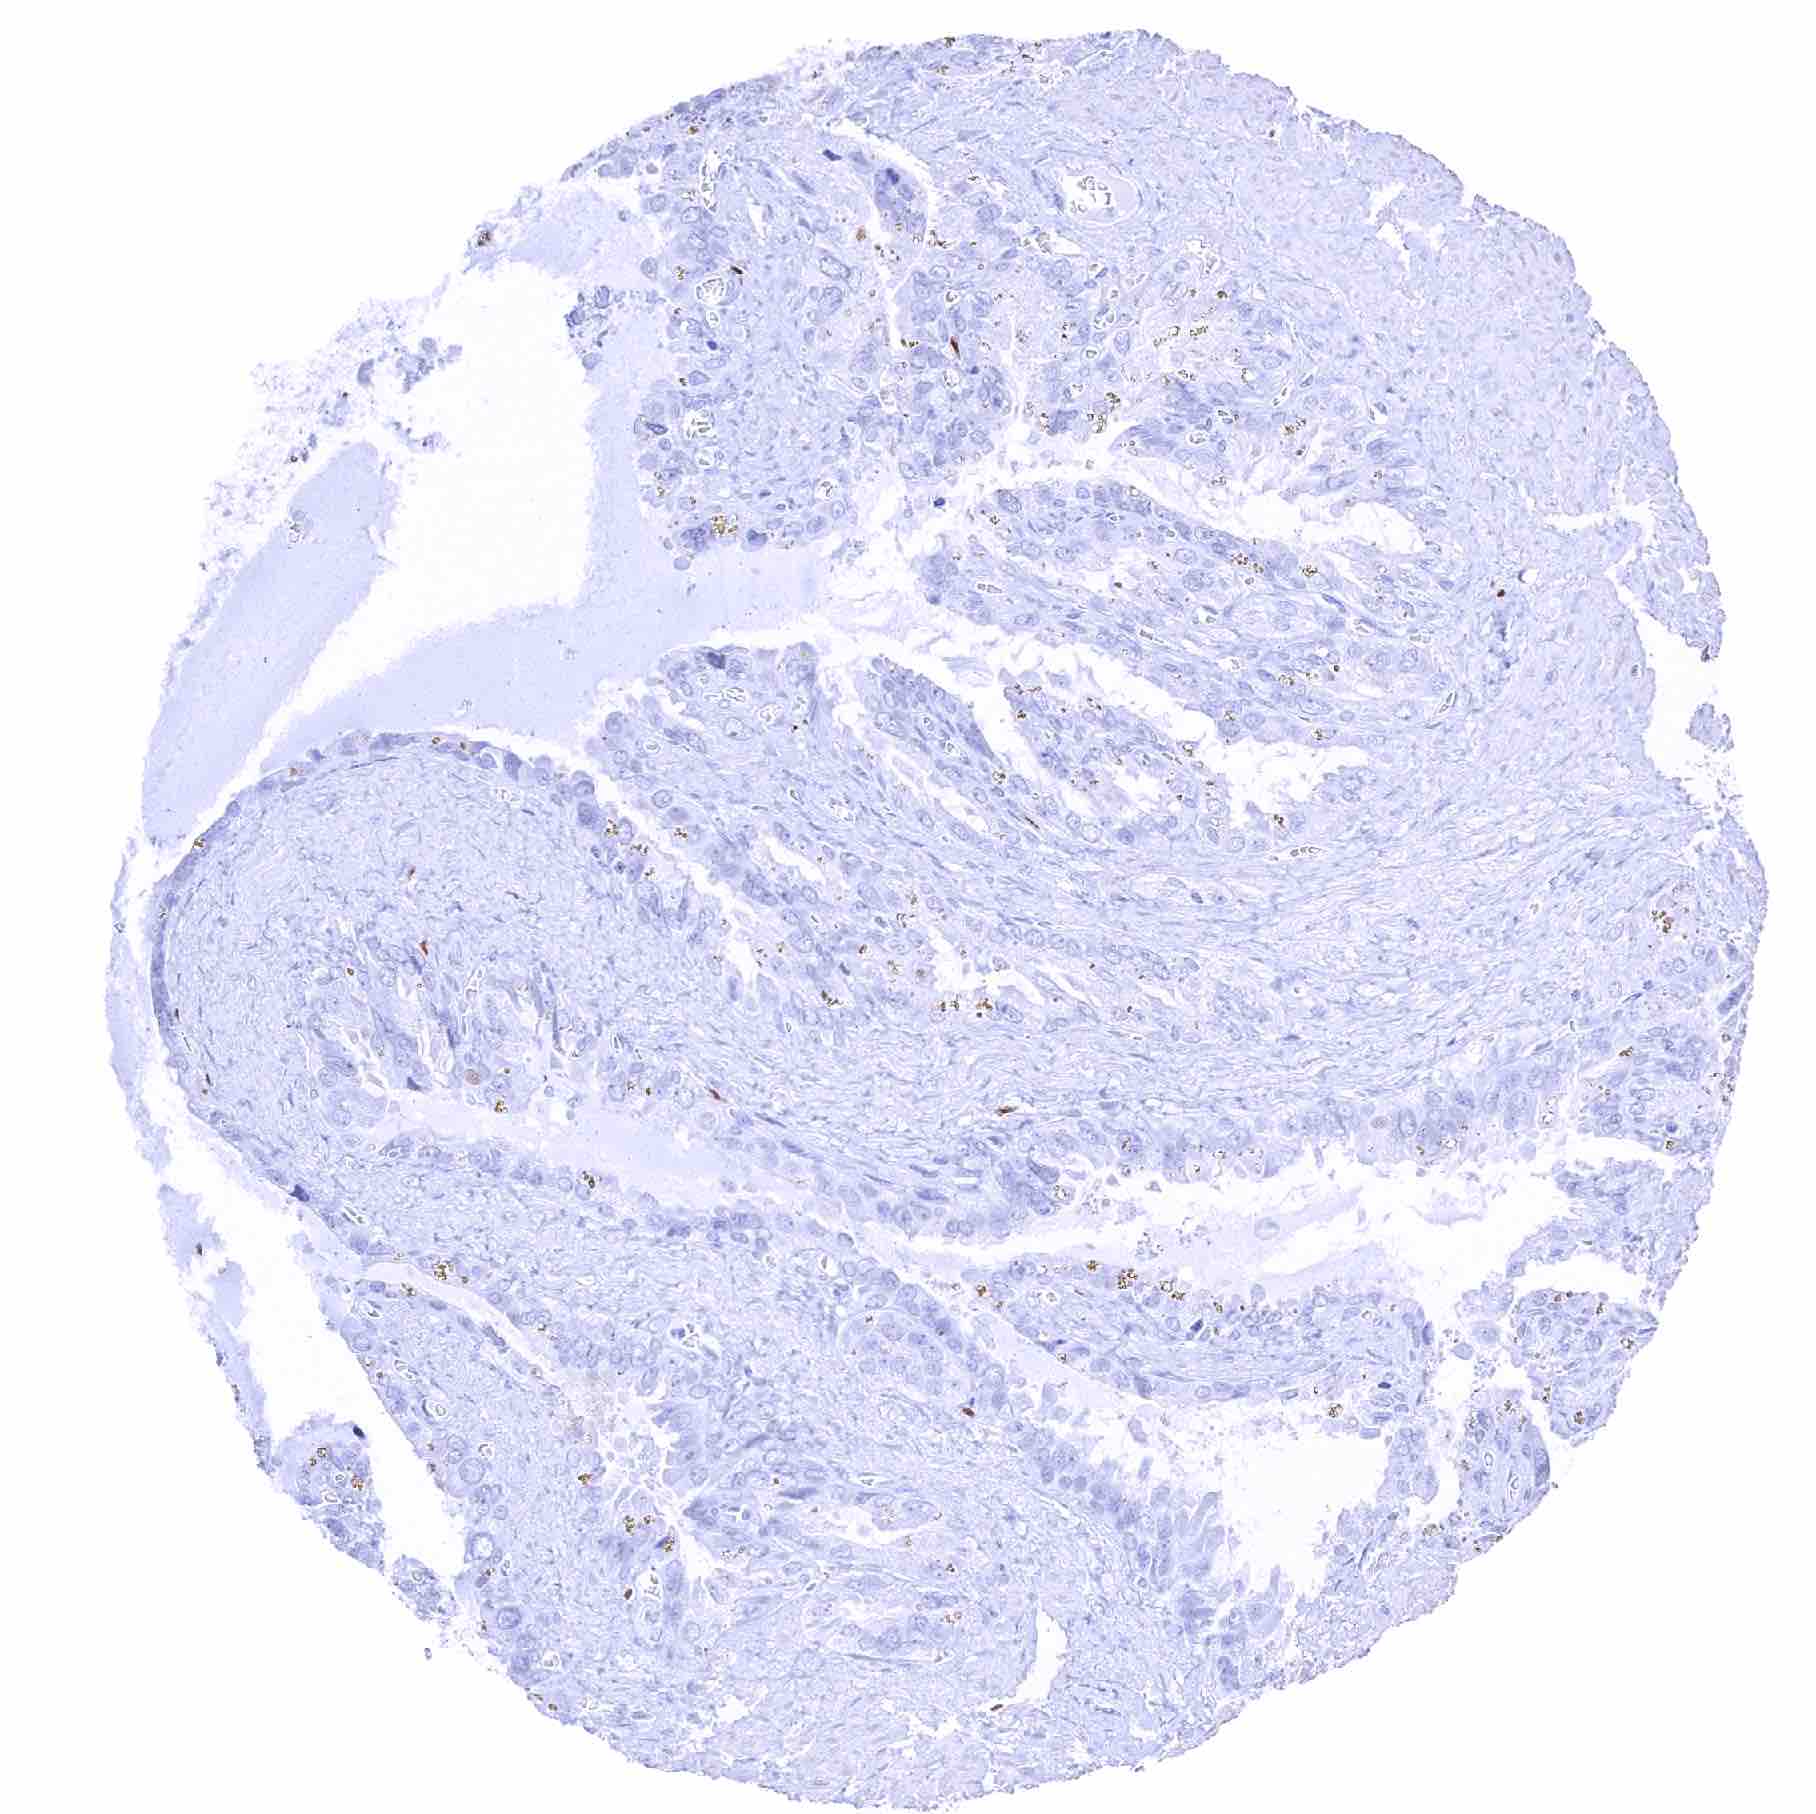

Prostate – Strong SOX2 positivity of a fraction of basal cells